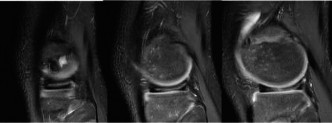

mechanical symptoms and swelling, reassurance is not appropriate. Although IT band tendonitis can cause “snapping” it is not accompanied by loss of extension and swelling. Corticosteroid injections should be utilized sparingly in the pediatric population; particularly when a diagnosis has not been made. The patient then obtains an MRI which is shown inFigure 10–30. The next appropriate step in management is:

Figure 10–30

The correct answer is (B). If the patient were asymptomatic, then the discoid meniscus could simply be observed with a return to unrestricted sporting activity. For a younger patient who is intermittently symptomatic and/or elects to not undergo operative intervention, lateral compartment unloader bracing may be appropriate until the patient and/or family agree to intervention. Long-leg casting is not appropriate and will do nothing more than cause stiffness, loss of strength, and range of motion. As the patient is symptomatic, has mechanical symptoms, and has potential tearing seen on MRI, arthroscopic intervention is indicated to examine the meniscus and intervene. The patient is taken to surgery, and intraoperative images ( Figs. 10–31 and 10–32 **) are shown. The next step in management is:**